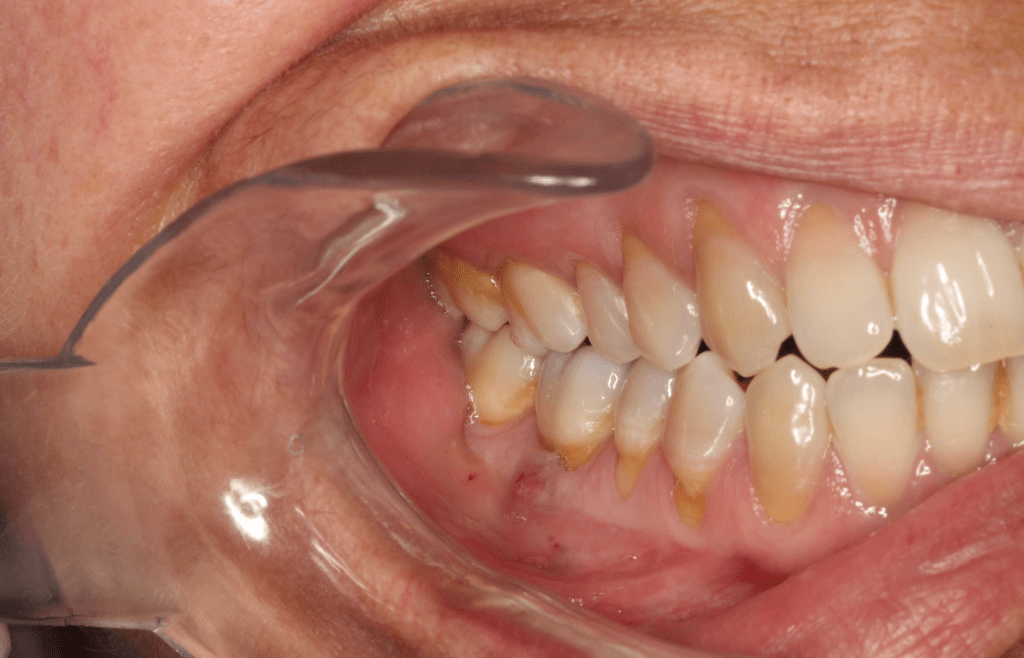

Diagnóstico de fisuras y fracturas

Diente fisurado regeneración total

Diente fisurado, no tratable

Diente fisurado tratable

Diente fisurado tratable con endodoncia

Diente fisurado tratable endodoncia 2

Fisura, remoción amalgama para explorar

Fractura cuspídea tratable

Vertical root fracture